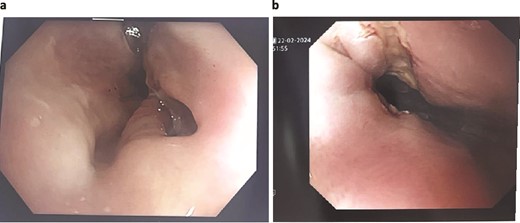

The patient was treated with antibiotics and VACStent insertions, requiring two stent placements (Fig. 1a). By the second stent removal, the anastomotic leak had closed (Fig. 1b). He experienced an episode of acute kidney injury managed with fluids. By postoperative day 24, the leak had resolved, the stent and porta Cath were removed, and the patient was discharged with normal blood results and a follow-up scheduled. The patient continued to manage his overall health with regular follow-ups.

Patient One: (a) Before VACStent insertion, showing the oesophageal defect. (b) After VACStent treatment, demonstrating successful defect closure.